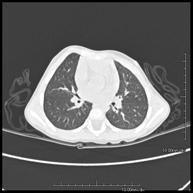

- TC Tórax alta resolución Prueba diagnóstica que consiste en el estudio del pulmón mediante el empleo de un equipo de TC (Tomografía Computarizada) obteniendo imágenes bi y tridimensionales que permiten un estudio anatómico altamente específico del pulmón, pudiendo valorar estructuras anatómicas de tamaño muy pequeño. Es una técnica muy importante en el estudio de los pacientes con sospecha de enfermedad pulmonar. Prueba diagnóstica que consiste en el estudio del pulmón mediante el empleo de un equipo de TC (Tomografía Computarizada) obteniendo imágenes bi y tridimensionales que permiten un estudio anatómico altamente específico del pulmón, pudiendo valorar estructuras anatómicas de tamaño muy pequeño. Es una técnica muy importante en el estudio de los pacientes con sospecha de enfermedad pulmonar.